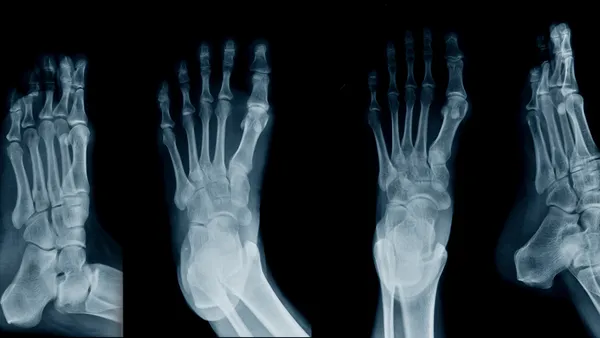

• Bunions (Hallux Valgus): Die pijnlijke bobbel aan de zijkant van je grote teen. Heb je aanleg? Dan kunnen knellende schoenen dit proces in een stroomversnelling brengen.

• Hielspoor (Fasciitis Plantaris): Een gebrek aan demping kan leiden tot felle, stekende pijn onder je hiel.

• Morton’s neuroom: Een beknelling van de zenuwen in de voorvoet, vaak veroorzaakt door smalle neuzen en hoge hakken. Het voelt alsof je constant op een kiezelsteentje loopt.

Kortom: dat ene feestje kan al de trigger zijn voor een blessure. Dr. Gregory Alvarez van Ankle and Foot Centers of America voegt toe dat acute blessures, zoals stressfracturen (kleine scheurtjes in het bot), al binnen enkele dagen kunnen ontstaan. Chronische aandoeningen, zoals de beruchte 'hamertenen' of eeltknobbels, zijn vaak het resultaat van langere verwaarlozing.